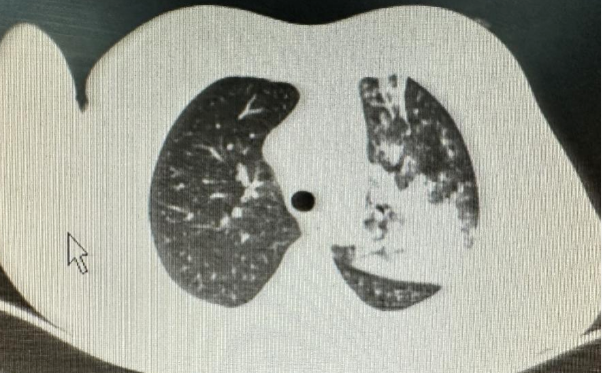

7岁女童,因“发热、咳嗽10天,加重2天”入院。院前曾予治疗,体温无明显好转,入院后治疗3天,体温稍好转,但咳嗽还在持续加重,复查肺部CT提示肺部炎症依旧控制不理想。